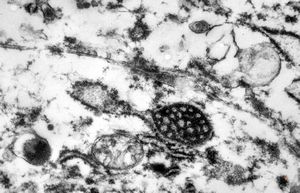

F, 7y. | molluscum contagiosum … virions

F, 7y. | molluscum contagiosum … virions